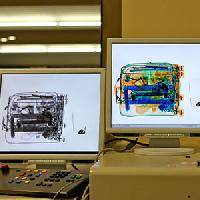

На рабочем месте производится обучение работе на Вашем оборудовании.

Любого доктора можно быстро подготовить как рентгенлаборанта и дать необходимые знания для оценки рентгенограмм.

Изучение проблемы низкого качества рентгенограмм на Вашем оборудовании.

Мобильный рентгенаппарат + оцифровщик. Получение рентгеновского изображения на экране ноутбука. Вариант за 1,4 миллиона рублей под ключ.

Мобильный рентгенаппарат с печатью рентгенограмм на рентгеновской пленке. Цена 700000 рублей.